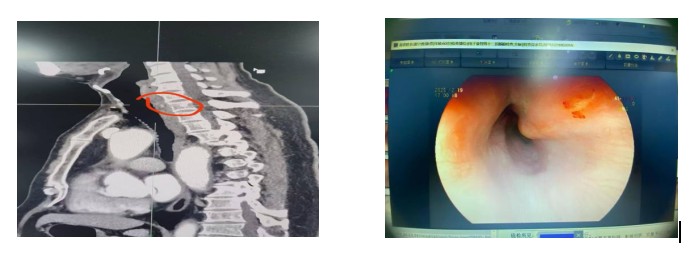

据了解,该患者进食时不慎误吞鱼刺,初期未予重视,还尝试用大量饭菜强行下咽,随后逐渐出现咽部剧痛、吞咽困难症状,甚至伴随胸部隐痛不适,遂在家属陪同下紧急前往南溪山医院消化内科就诊。经胃镜及食管 CT 检查确诊,一根鱼刺已完全刺入食管壁,诱发局部黏膜充血水肿,且形成局限性脓肿,鱼刺深埋食管壁内无法通过普通内镜直接观察,若延误治疗,极有可能引发食管穿孔、纵隔感染等致命并发症,危及生命安全。

考虑到传统外科手术创伤大、恢复周期长,会给患者带来较大身心负担,消化内科医疗团队第一时间组织病例研讨,结合患者病情精准评估,最终敲定内镜下微创治疗方案。手术中,医护团队凭借精湛内镜操作技术,先通过超声胃镜精准锁定鱼刺埋藏位置,再运用 ESD 技术小心切开局部黏膜,借助圈套器、异物钳精准操作,将刺入食管壁的鱼刺完整取出,随后对脓肿部位进行彻底引流。整个手术过程顺利,耗时短、创伤小,患者术中无明显不适感。